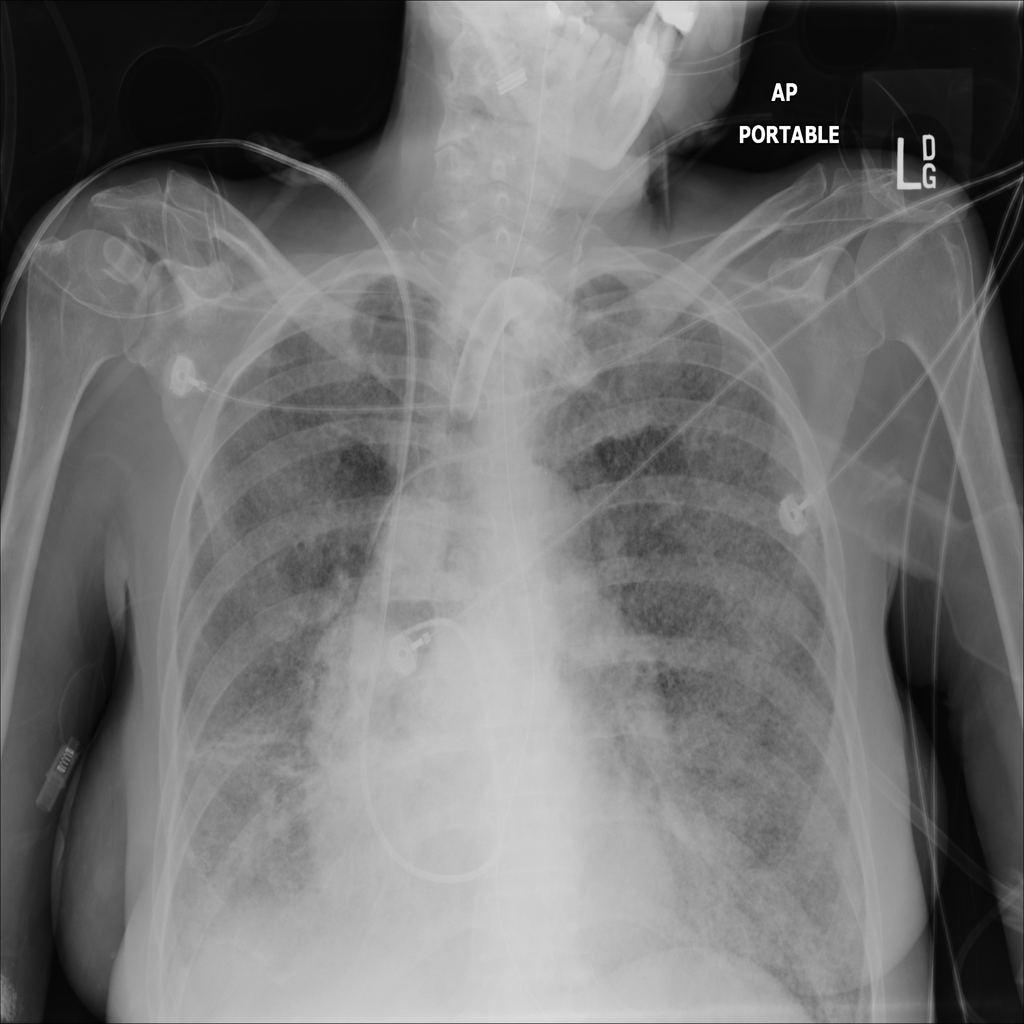

PAT-E1D6 · IMG-065Fibrosis

PAT-E1D6 · IMG-065

AP